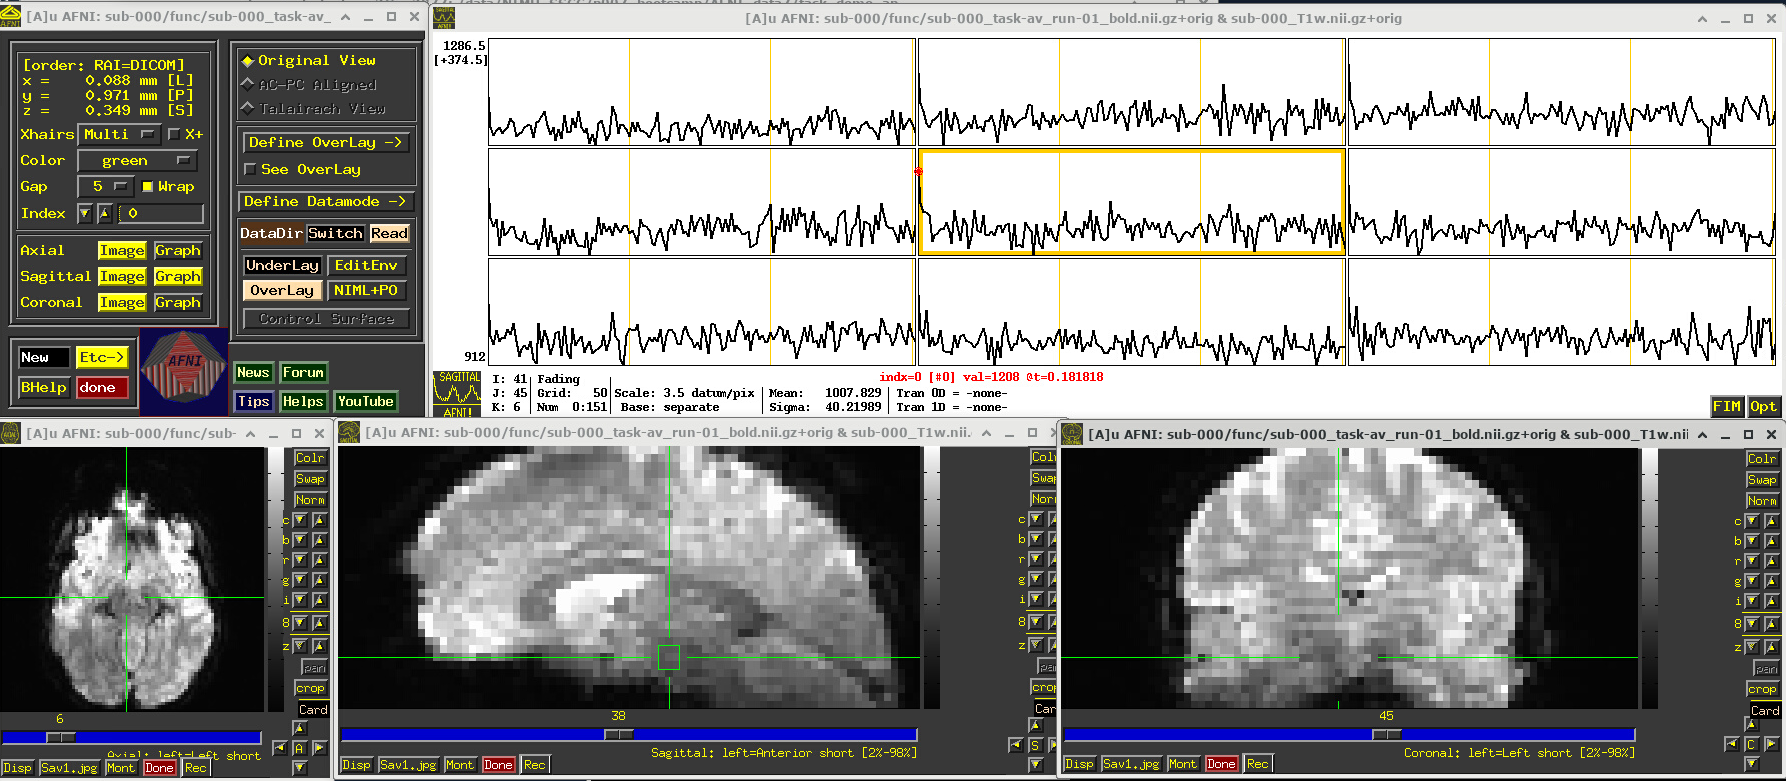

A screenshot of the described GUI setup is shown, below.

In the Image panels, you see a fuzzy-looking brain, with some cortical patterns visible, but tissue boundaries and regions probably aren’t as obvious as in the anatomical dataset view, above.

In the Graph panel, you are seeing a montage of time series from a (default) 3x3 grid of voxels in the given sagittal slice. In this subcortical region, the time series have a lot of fluctuations and don’t have a recognizable pattern.

# Display a screenshot of the AFNI GUI with the first EPI run loaded, seen at coordinate origin

IPython.display.Image(filename='example_snapshots/img_01_afnigui_epi_r01_000.png')

../_images/230cc87850086d0cc51017fcc155a583ecb39e569916ab90b26550ade057de65.png